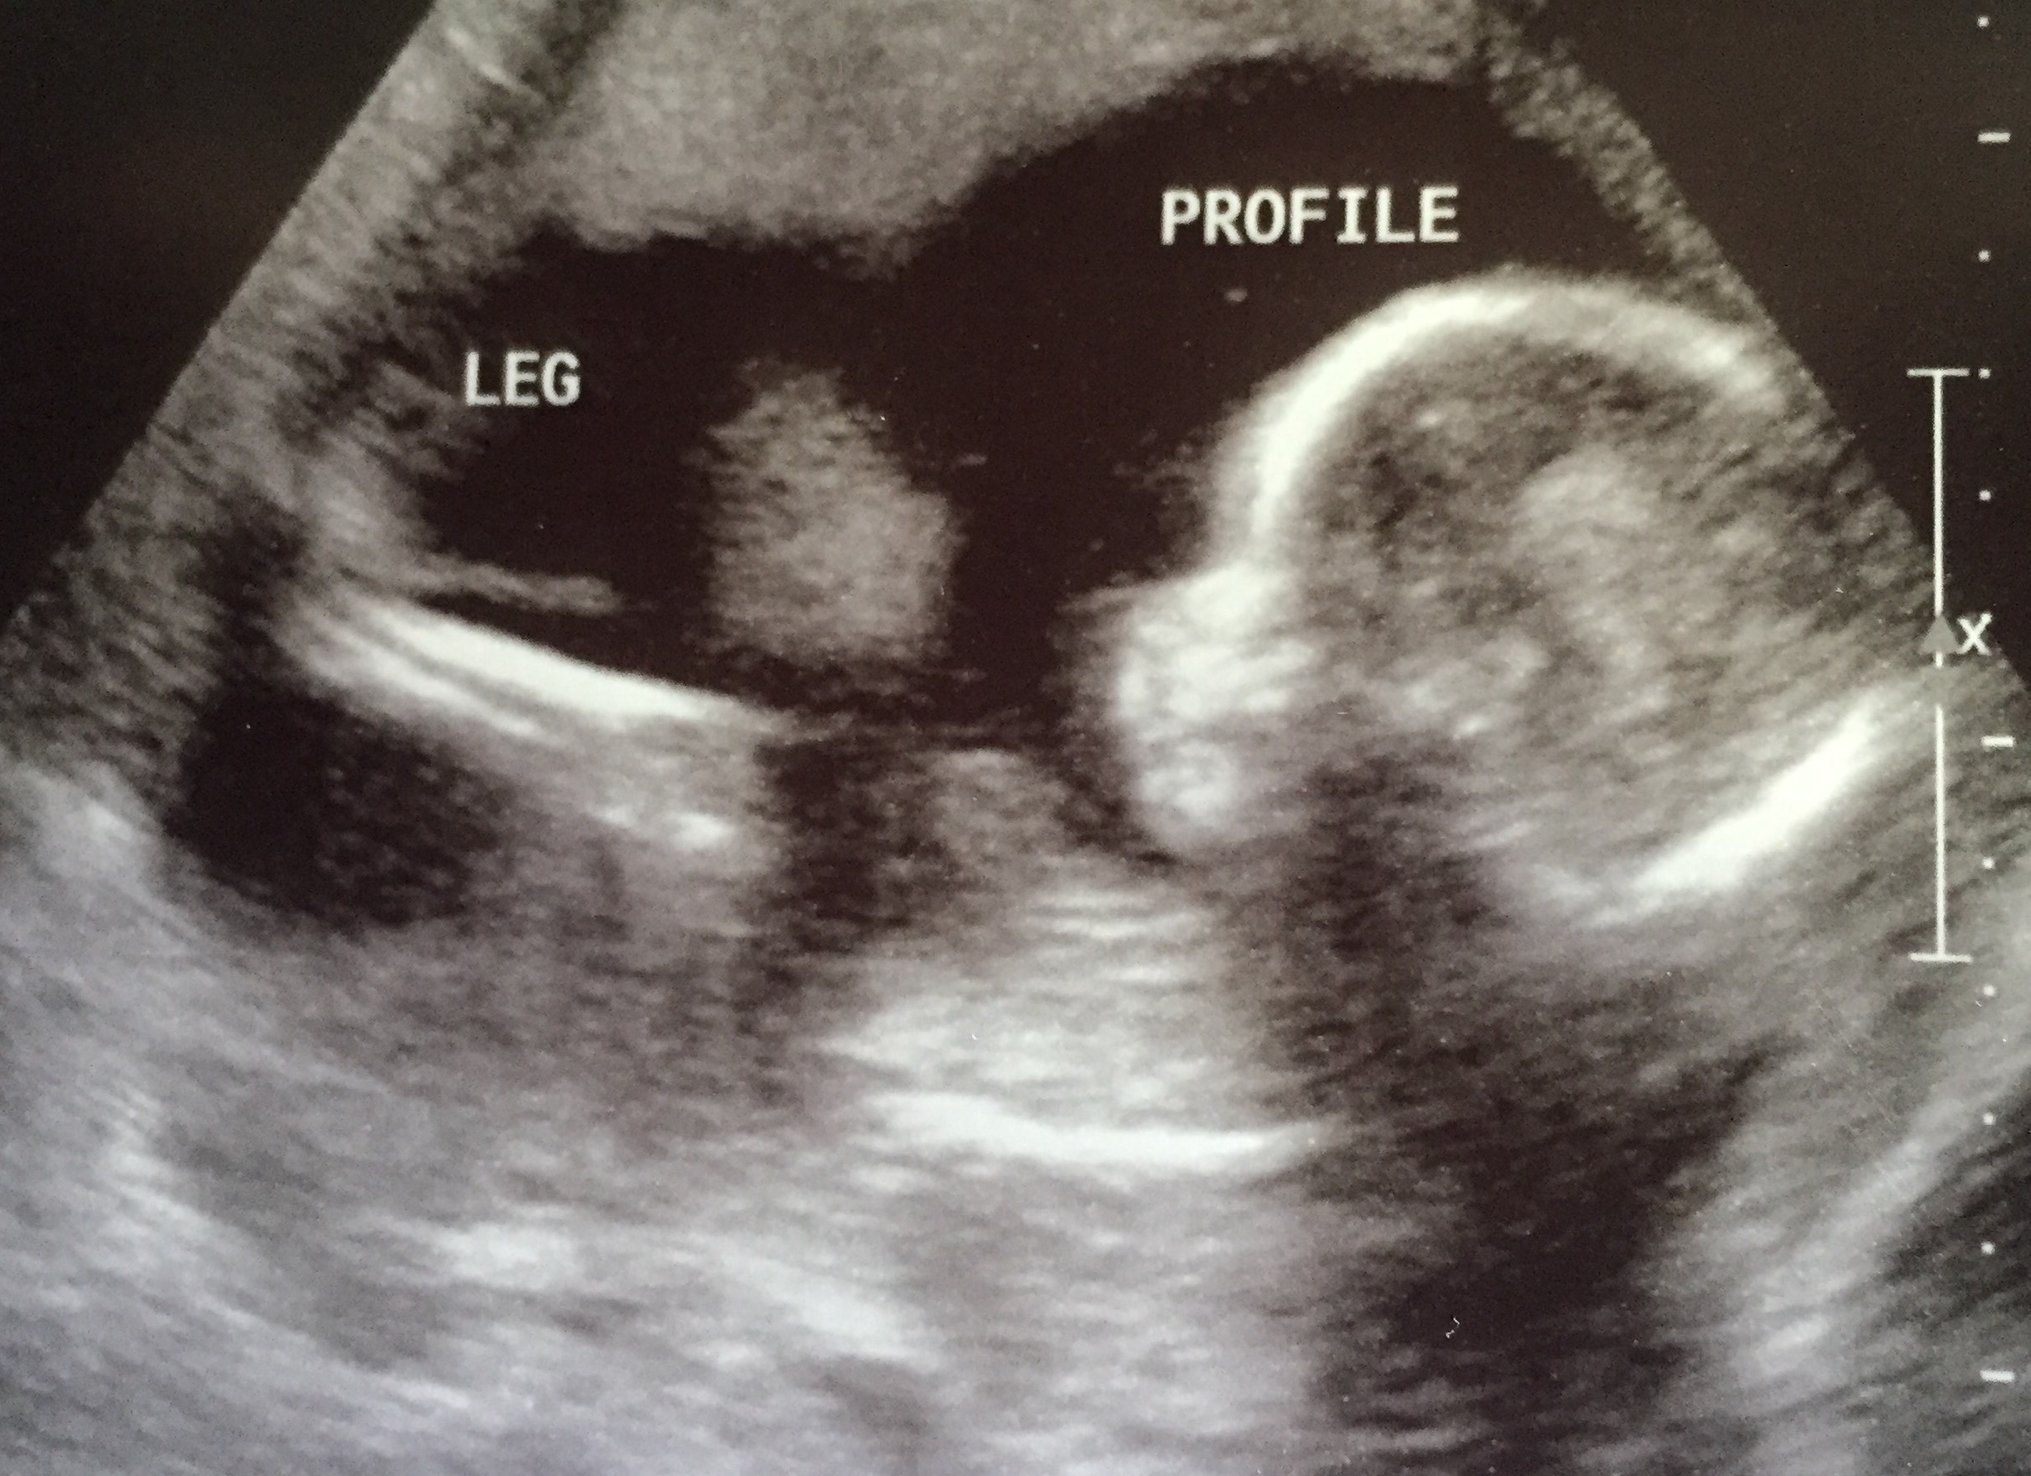

Baby H at my 18w U/S yesterday... After over an hour of looking and measuring and not being able to see the sex due to LO keeping the legs crossed, I was told to empty my bladder and we would try again. LO not only uncrossed it's legs, but completely flipped over... It's a Girl!